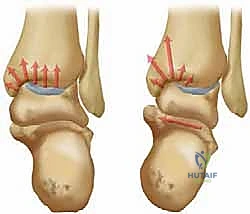

عندما يصاب هذا المفصل بالخشونة (التهاب المفاصل التنكسي)، فإن التأثير على جودة حياة المريض يكون كارثياً. يتحول المشي من حركة لا إرادية بسيطة إلى مهمة شاقة ومؤلمة. إحدى الحالات الميكانيكية الأكثر شيوعاً وتعقيداً هي خشونة مفصل الكاحل من النوع التقوسي (Varus Ankle Osteoarthritis)، والتي تتميز بتشوه في المفصل يؤدي إلى ميلان القدم للداخل وتركز الضغط الهائل على الجانب الداخلي (الإنسي) من المفصل، مما يؤدي إلى تآكل الغضاريف بشكل متسارع.

في حالة التشوه التقوسي (Varus Deformity)، يحدث ميلان في المحور الميكانيكي للساق. تخيل أنك تقود سيارة وإطاراتها غير متوازنة (Misaligned). سيؤدي ذلك إلى تآكل جانب واحد من الإطار بسرعة أكبر بكثير من الجانب الآخر. هذا بالضبط ما يحدث في الكاحل التقوسي؛ حيث ينتقل محور تحمل الوزن (Weight-bearing axis) بشكل غير طبيعي نحو الداخل (الجانب الإنسي). هذا التركيز المفرط للإجهاد يفوق قدرة الغضروف على التحمل، مما يؤدي إلى تشققه، تآكله، وفي النهاية تلامس العظم بالعظم، وهو ما يسبب الألم المبرح والالتهاب.

تكمن المشكلة الأساسية في خشونة مفصل الكاحل من النوع التقوسي في تركز الإجهاد على الجانب الإنسي. هدف جراحة قطع العظم التي يجريها الدكتور هطيف ليس فقط إيقاف هذا التدهور، بل وإعطاء الجسم فرصة لإصلاح عيوب الغضروف جزئياً عن طريق تشكيل نسيج غضروفي ليفي (Fibrocartilage) بمجرد إزالة الضغط الميكانيكي عنه.